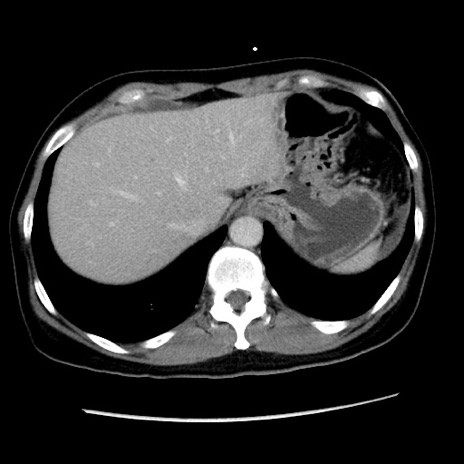

症例10(横断像)

【症例】 50歳代女性

【主訴】 腹痛

【現病歴】前日生レバーを食べた。今朝に排便あり。 昼前に突然発症の腹痛を生じ、当院救急外来を受診した。

【身体所見】 意識清明、腹部:平坦、軟、下腹部やや左を中心に圧痛・反跳痛あり、筋性防御あり

【データ】WBC 7800、CRP 0.07